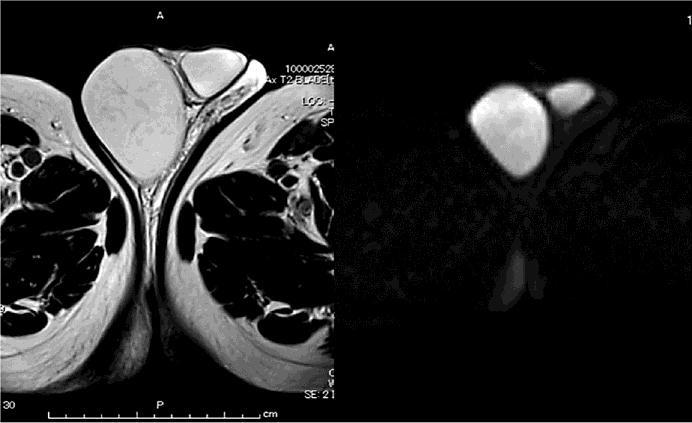

A 66-year-old male was referred to our hospital for further examination of a scrotal mass. Because of the risk of testicular cancer, we first clamped the vessels as a course of higher orchiectomy. Then, we approached the tumor through the scrotum and successfully resected it while preserving the testis. A histopathological diagnosis revealed an epidermal cyst. We herein report a rare case of an intrascrotal epidermal cyst successfully treated while preserving the testis.

一名66岁男性因阴囊肿物被转诊至我院做进一步检查。鉴于存在睾丸癌风险,我们首先结扎血管,作为高位睾丸切除术的一个步骤。然后,我们经阴囊入路接近肿瘤,成功将其切除,同时保留了睾丸。组织病理学诊断为表皮样囊肿。我们在此报告一例罕见的阴囊内表皮样囊肿,成功保留睾丸进行治疗的病例。